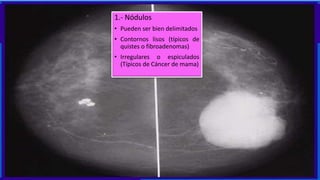

1.- Nódulos

• Pueden ser bien delimitados

• Contornos lisos (típicos de

quistes o fibroadenomas)

• Irregulares o espiculados

(Típicos de Cáncer de mama)

1.- Nódulos • Puedenser bien delimitados • Contornos lisos (típicos de quistes o fibroadenomas) • Irregulares o espiculados (Típicos de Cáncer de mama)